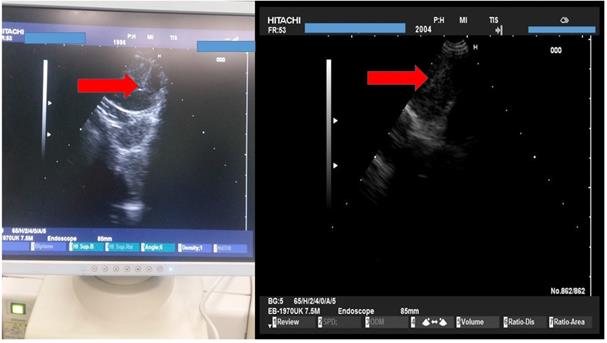

We used the tip of the convex probe to visualize the lesion and we punctured the mass and injected the two drugs. Firstly cisplatin was applied and then nivolumab or pembrolizumab in three different sections of the lesion. We administered the immunotherapy drugs after cisplatin in every puncture, by doing this we did less punctures and we induced higher local treatment efficiency with the combination (Figure 4).

Figure 4

HITACHI EUB-7000EB images from different patients during administration.